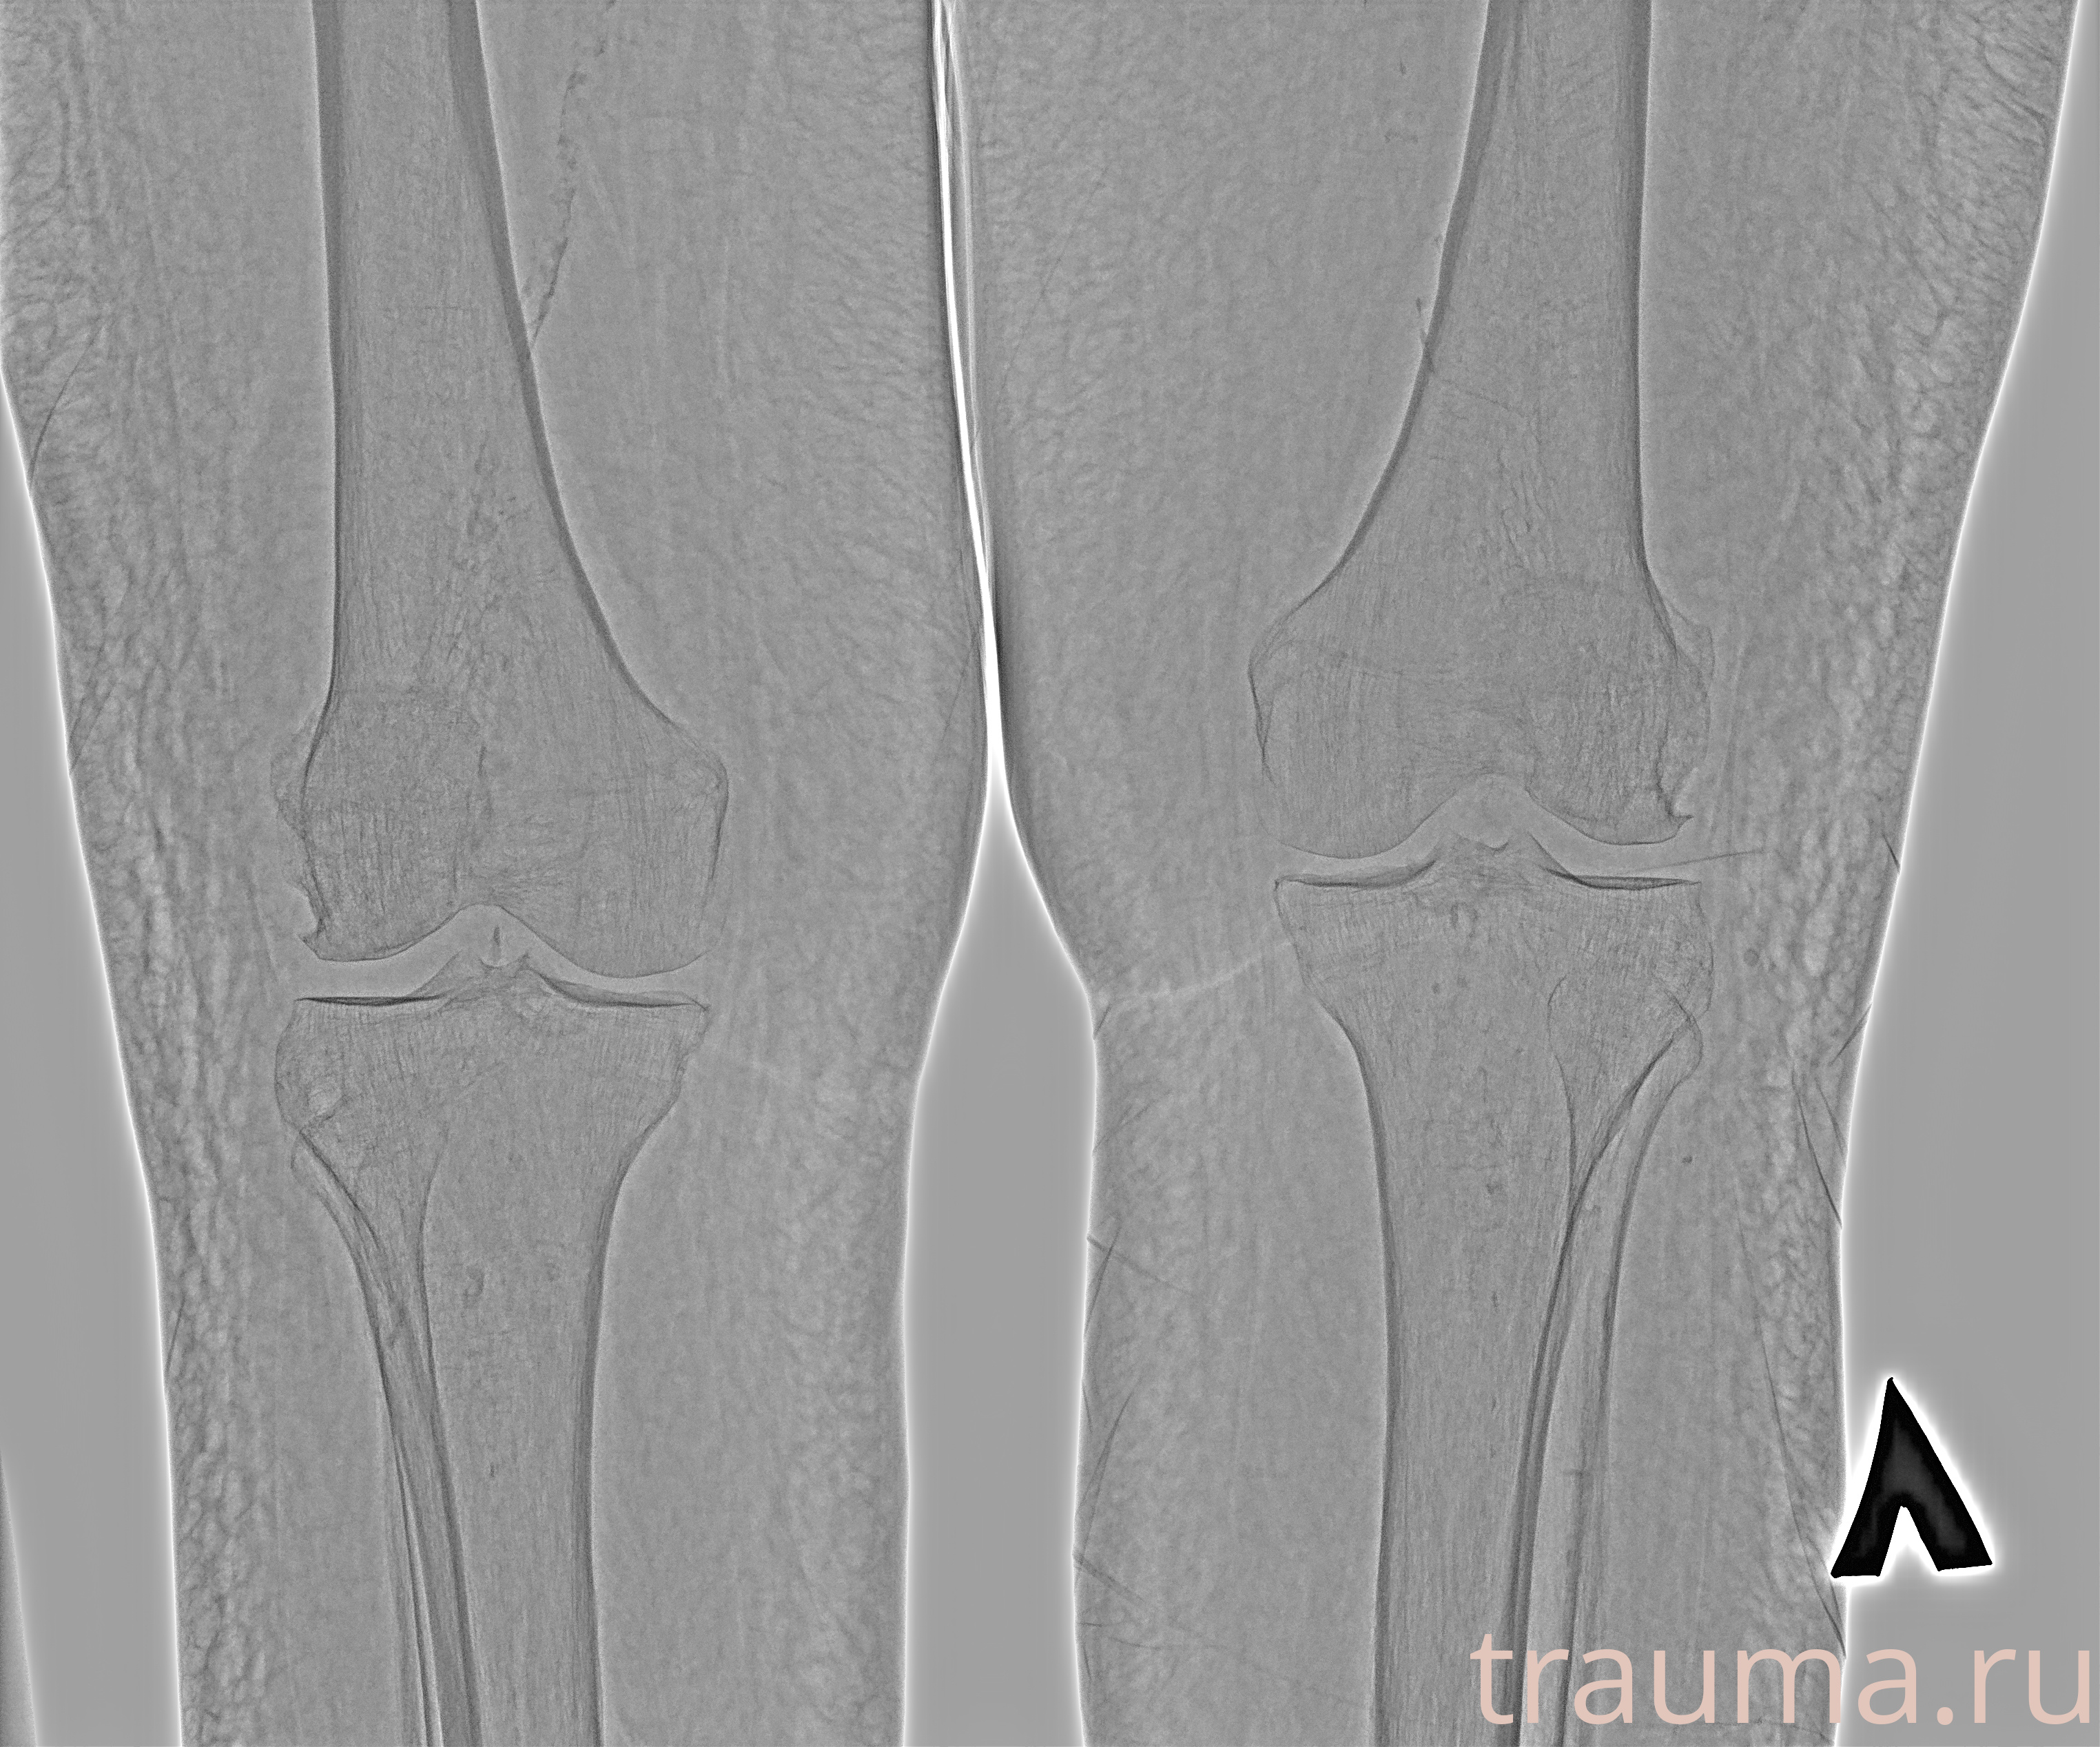

Рентгенограммы

Рентген на дому: по вашему адресу приезжает врач-рентгенолог, травматолог-ортопед с мобильным рентгеновским аппаратом, проводит диагностику травмы или заболевания, делает необходимые рентгенограммы, дает рекомендации по дальнейшему лечению. Получить качественные снимки в домашних условиях возможно благодаря уникальной методике, разработанной МосРентген Центром для института  Склифосовского